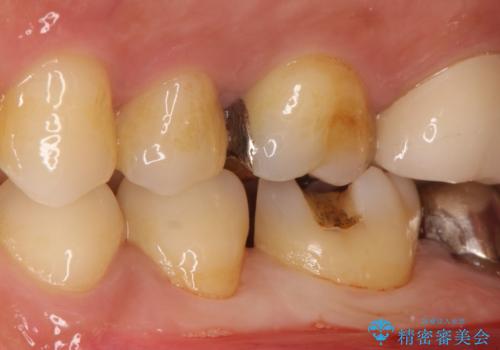

- 金属の詰め物が外れたことを主訴に来院されました。

隣の歯もむし歯を認め、セラミックインレーとセラミッククラウンにて治療を行なっております。